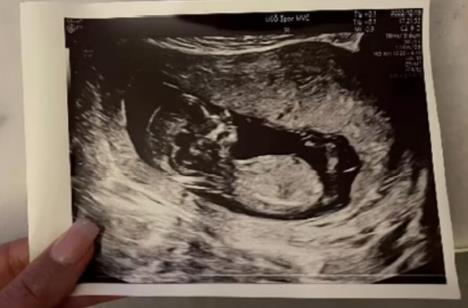

Ovakav slučaj dogodio se jednoj ženi, koja je u 51. godini saznala da je trudna. Priču je podelila njena poznanica na društvenoj mreži X, a izazvala je lavinu komentara.

Ona je za trudnoću saznala tek u petom mesecu, što je predstavljalo veliki šok za celu porodicu.

- Moja poznanica, stara 51 godinu, saznala je da je trudna u 5. mesecu. Deca joj završavaju faks, oduševljeni. Ona i muž plaču na smenu. Inače poslednja dva meseca išla kod lekara, od gastro do urologa. Trudnoća, nikom ni pala napamet, jer menopauza. I tako - napisala je jedna korisnica mreže X.